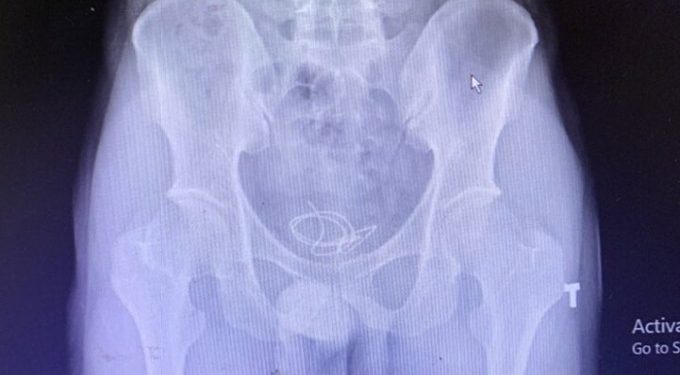

QUẢNG NINHNam thanh niên 25 tuổi nhập viện trong tình trạng đi tiểu khó và buốt, ảnh chụp X-quang phát hiện một đoạn dây đeo tai nghe (headphone) dài 20 cm.

Bác sĩ Nguyễn Như Trung, Khoa Ngoại thận tiết niệu, Bệnh viện Việt Nam – Thụy Điển Uông Bí. ngày 10/6 cho biết đoạn dây nằm cuộn lại tại bàng quang của bệnh nhân làm tổn thương bàng quang, gây viêm niệu đạo.